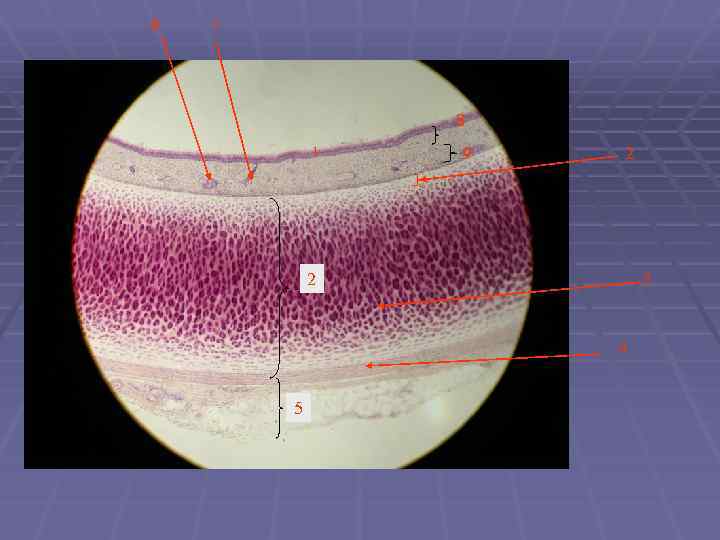

Препарат: Трахея Окраска: гематоксилин-эозин Увеличение: малое 1 – слизистая оболочка 2 – подслизистая оболочка 3 – фиброзно хрящевая оболочка 4 – адвентициальная оболочка 5 – поперечный срез нерва 1 2 3 5 4